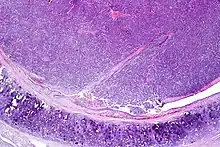

| Atypical pulmonary carcinoid. H&E stain. | |

Atypical carcinoid tumors have increased mitotic activity (2-10 per 10 HPF), nuclear pleomorphism or foci of necrosis.

Atypical carcinoid of the lung exhibiting endobronchial growth, increased mitotic activity was seen (2-10 per 10 HPF). H&E stain.